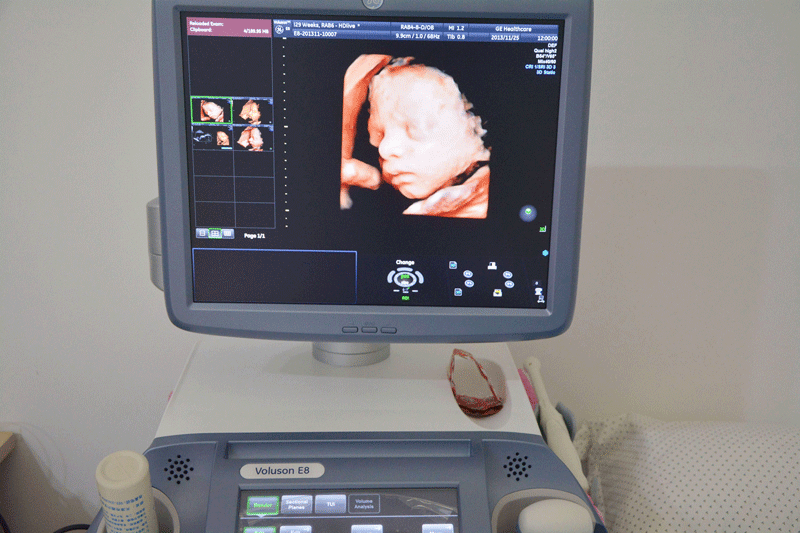

三维彩超,即彩色多普勒超声检查的一种,检查图像呈土黄色,通过多普勒超声仪器发出超声波,对体内各项器官进行成像。三维即其图像是立体的,可以更直观的看到器官的形态,及时发现病变并进行治疗。三维彩超常用于产检,用来判断胎儿的生长发育的情况或是否出现畸形等。

产检中,三维彩超通过测量子宫纵径、子宫体横径、子宫前后径这三条径线来观察胎儿是否正常。以及通过三维立体的成像,可以清晰的显示出胎儿各个内脏器官,以及面部器官、四肢的情况,来简单的判断胎儿是否存在畸形,包括胎儿是否患有先天性心脏病也是能够检查出来的。

24周的胎儿,其身体结构的生长发育已经很完善了,且胎儿大小也很合适,这时候做三维彩超可以很直观的看到胎儿的五官四肢、以及内脏器官,还能了解胎儿双顶径、头围、腹围、股骨长等发育情况。

2、清晰度不同

目前临床上三维彩超检查是直接对胎宝宝先天头面部畸形的判断,可以拍到宝宝生长发育的局部立体图像。而四维相对于三维来说,会更清晰,对胎宝宝畸形,如唇腭裂、四肢发育畸形、脑膜膨出、脊柱裂、腹壁裂和心血管畸形等能够做早期诊断,并且能够立体显示胎宝宝的颜色、各器官的发育情况,甚至在母体内吸吮、睡觉等动态也可以捕捉到。。

三维和四维并不是彩色图片,只是和黑白色有差异,二者呈现的都是土黄色的画面。但三维的成像是静态的,是一张图片,而四维彩超则是动态的,像一张动图一样,并且有的医院会允许刻成光盘带回家收藏起来。